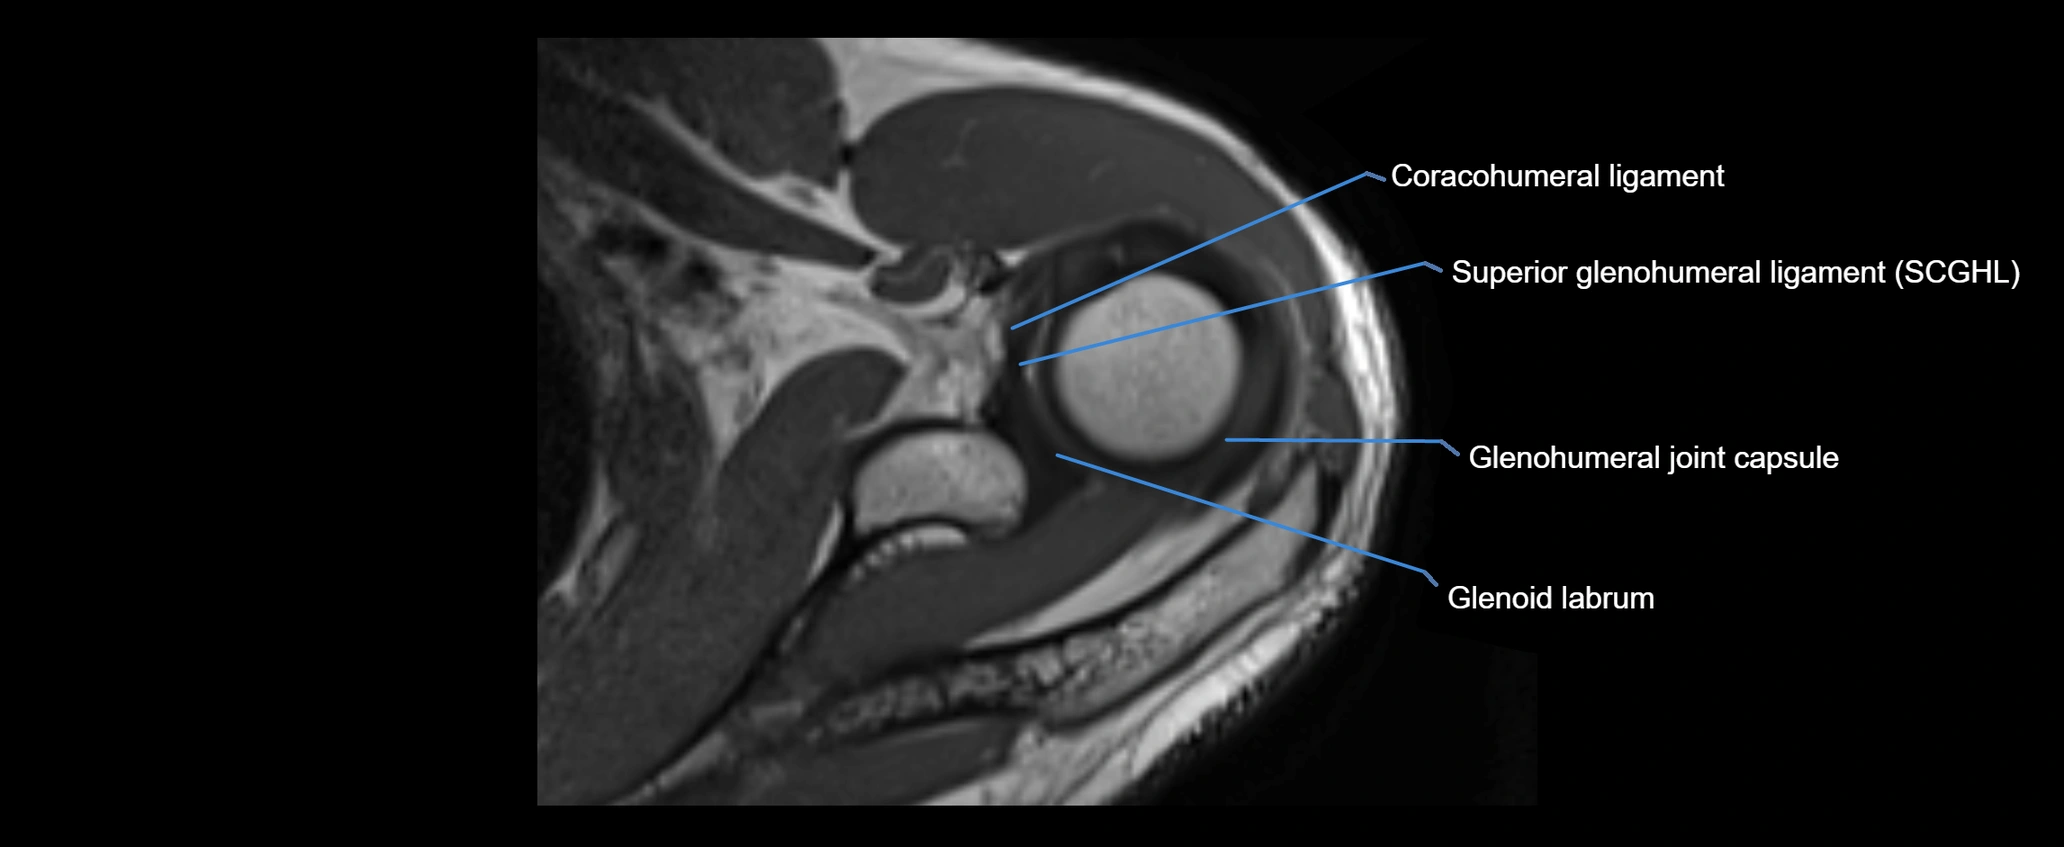

MRI images

image